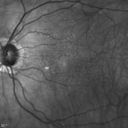

FUNDUS PHOTOGRAPHY - INFRA RED: The image shows reticular pseudo drusen in both eyes.